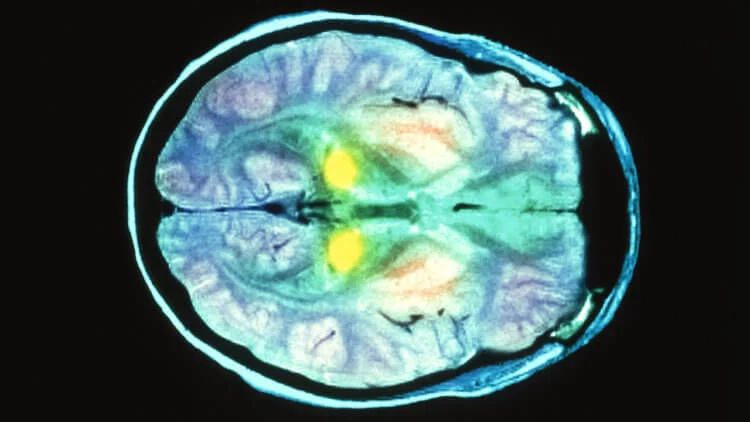

Нейродегенеративные заболевания, вызваны прионами, буквально превращают мозг в губку.

Так выглядят прионы – Белковые соединения с определённой конфигурацией, способные трансформироваться в патогенные и вызывать нейродегенеративные процессы в головном мозге.

Сканирование мозга пациента с болезнью Крейтцфельдта-Якоба.